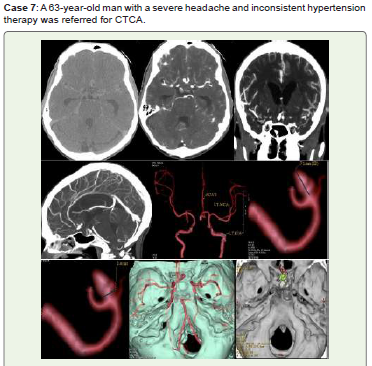

Figure 7:Noncontrast CT (A), shows acute SAH. A medium saccular

aneurysm of ACOM with a neck diameter of 3.4 mm is visible on CTCA (B-D),

3D-VR pictures (E-G), and 3D-VR virtual dissection (H, I).

Endovascular coiling and/or surgical clipping were recommended for him.